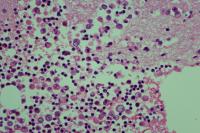

男,78岁,胸水腺癌?

性别

男

年龄

78岁

一般病史

胸腔积液,肺不张,肺部感染

标本类型

胸水

制片方法

涂片

染色方法

HE

会诊意见:良性的。

细胞蜡块可以标记看看

未见肿瘤细胞。

图9~~图13是细胞蜡块